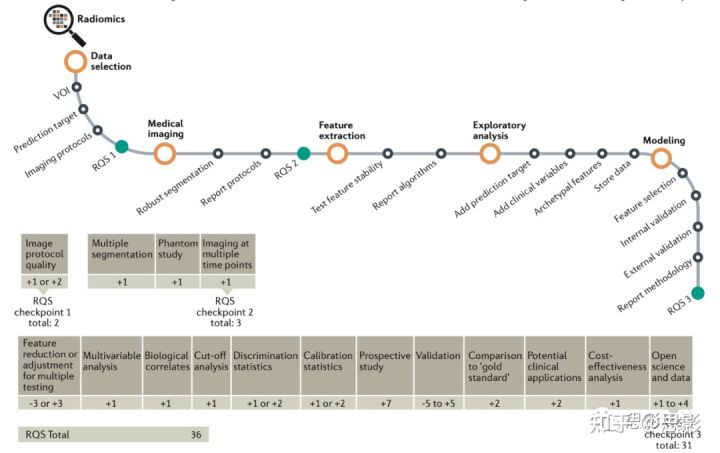

影像组学方法被定义为定量映射,即提取与预测目标相关的许多医学图像特征如临床和基因组特征并建模分析。影像组学研究可分为五个阶段:数据选择、医学成像、特征提取、探索性分析和建模(图1)。为了评估影像组学研究的质量,我们提出了影像组学质量评分(RQS)。

图1:描述影像组学实现流程图和RQS应用的流程图。

该流程包括影像组学分析中的必要步骤。RQS对研究方法和分析进行评分,从而鼓励最佳科学实践。RSQ,影像质量评分;VOI,感兴趣区。